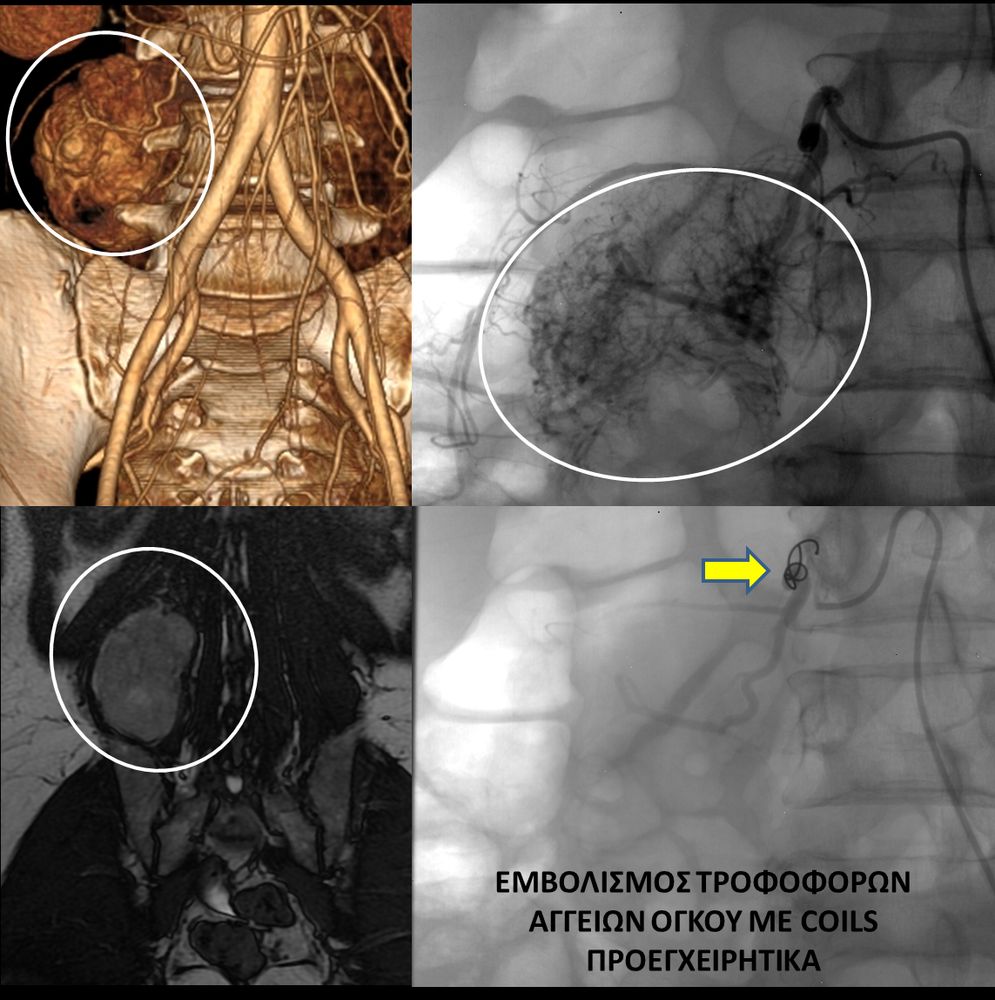

♦ Όγκους

Είτε προεγχειρητικά για την ελάττωση της αιμάτωσης του όγκου, είτε θεραπευτικά σε ορισμένες περιπτώσεις που δεν απαιτείται χειρουργείο ή υπάρχει αντενδειξη για χειρουργική αφαίρεση του όγκου.

Συνοπτικά υπό την καθοδήγηση του αγγειογράφου, αναγνωρίζεταιτο παθολογικό αγγείο-αγγεία και με ειδικούς καθετήρες και μικροκαθετήρες, διοχετεύονται εμβολικά υλικάόπως μικροσφαιρίδια ή coils, ώστε να αποφραχθεί ή να μειωθεί η παθολογική αγγείωση.